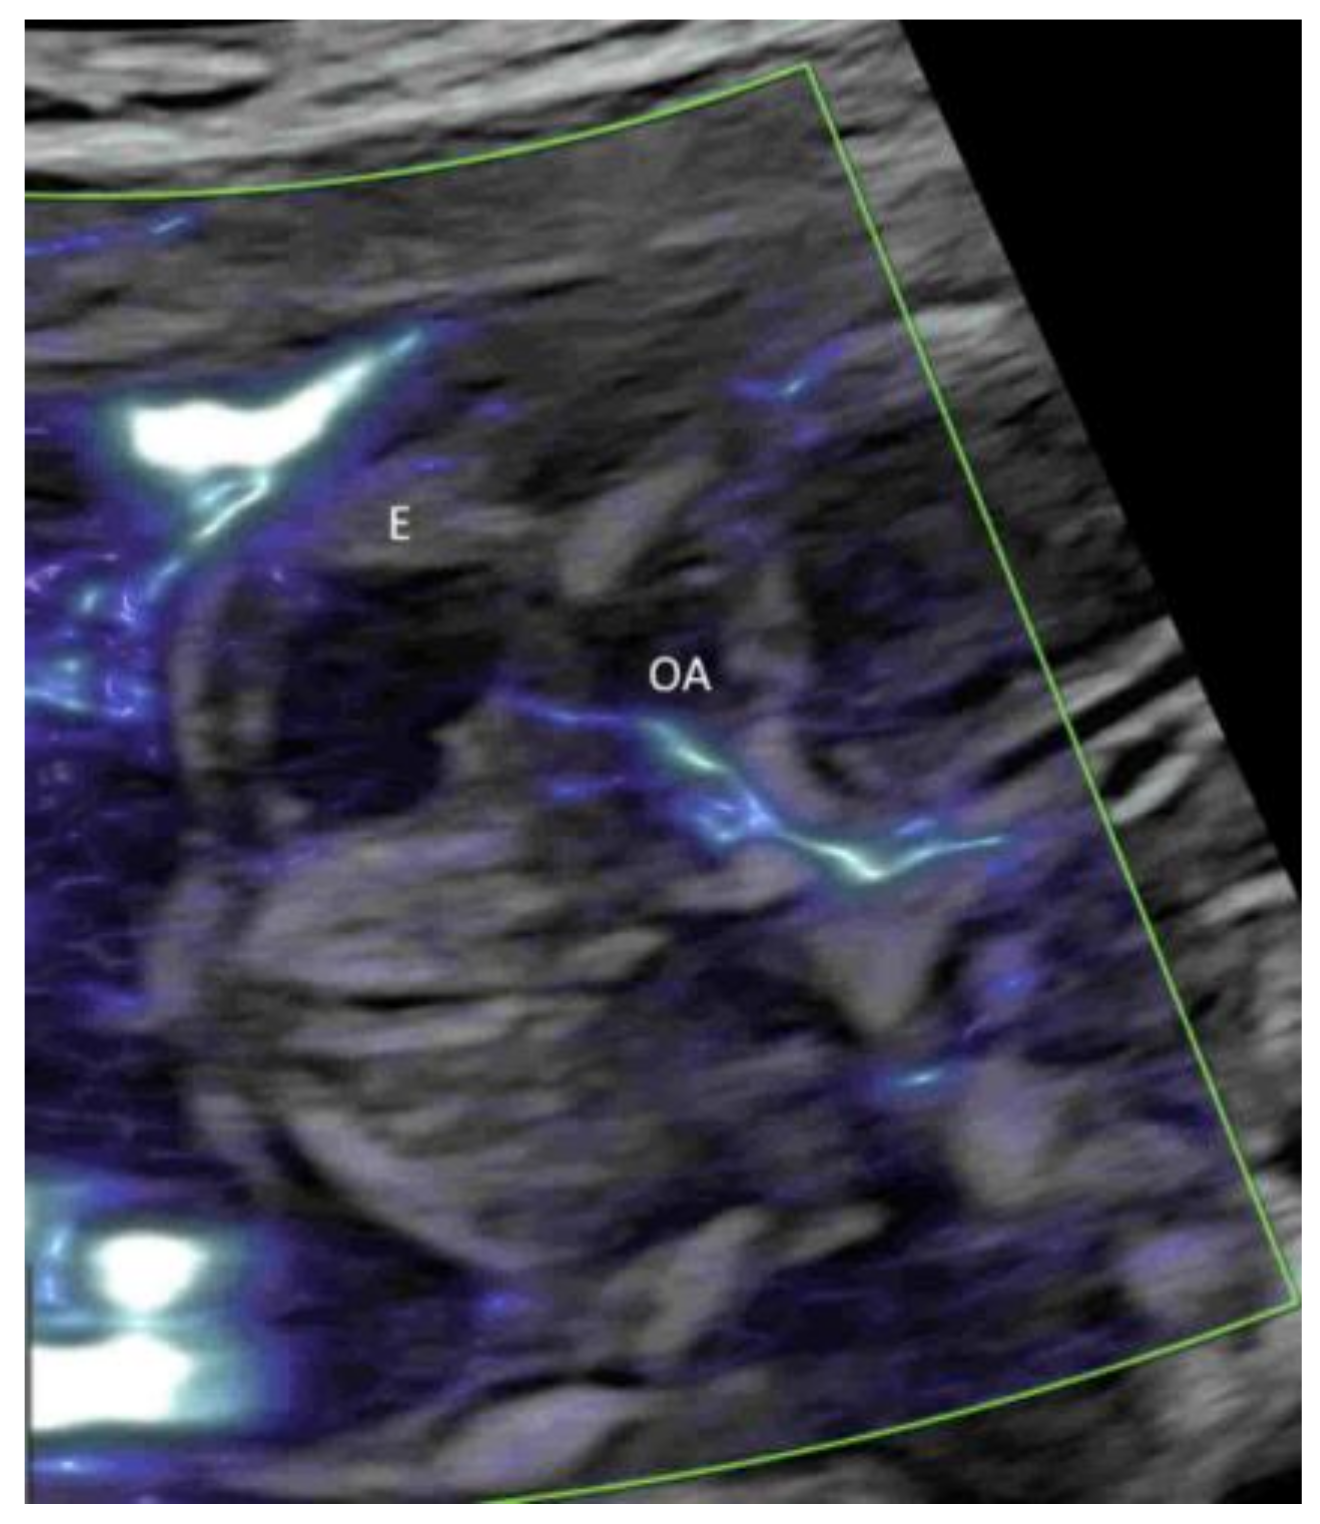

- Hasegawa, J.; Yamada, H.; Kawasaki, E.; Matsumoto, T.; Takahashi, S.; Suzuki, N. Application of superb micro-vascular imaging (SMI) in obstetrics. J. Matern. Fetal Neonatal Med. 2018, 31, 261–263. [Google Scholar] [CrossRef]

- Mack, L.M.; Mastrobattista, J.M.; Gandhi, R.; Castro, E.C.; Burgess, A.P.H.; Lee, W. Characterization of Placental Microvasculature Using Superb Microvascular Imaging. J. Ultrasound Med. 2019, 38, 2485–2491. [Google Scholar] [CrossRef]

- Sainz, J.A.; Carrera, J.; Borrero, C.; García-Mejido, J.A.; Fernández-Palacín, A.; Robles, A.; Sosa, F.; Arroyo, E. Study of the Development of Placental Microvascularity by Doppler SMI (Superb Microvascular Imaging): A Reality Today. Ultrasound Med. Biol. 2020, 46, 3257–3267. [Google Scholar] [CrossRef]